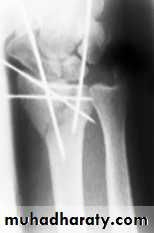

3-IMPACTED OR COMMINUTED COLLES’ FRACTURESWith substantial impaction or comminution in osteoporotic bone, manipulation and plaster immobilization alone may be insufficient. The fracture can sometimes be reduced and held with percutaneous wires, but if impaction is severe even this may not be enough to maintain length; in that case, an external fixator is used to neutralize the compressive force of the 25 tendons crossing the wrist, and bone graft or bone substitute is placed into the gap. The fixator is attached to the distal radius and the second metacarpal shaft.

IMPACTED OR COMMINUTED COLLES’ FRACTURES